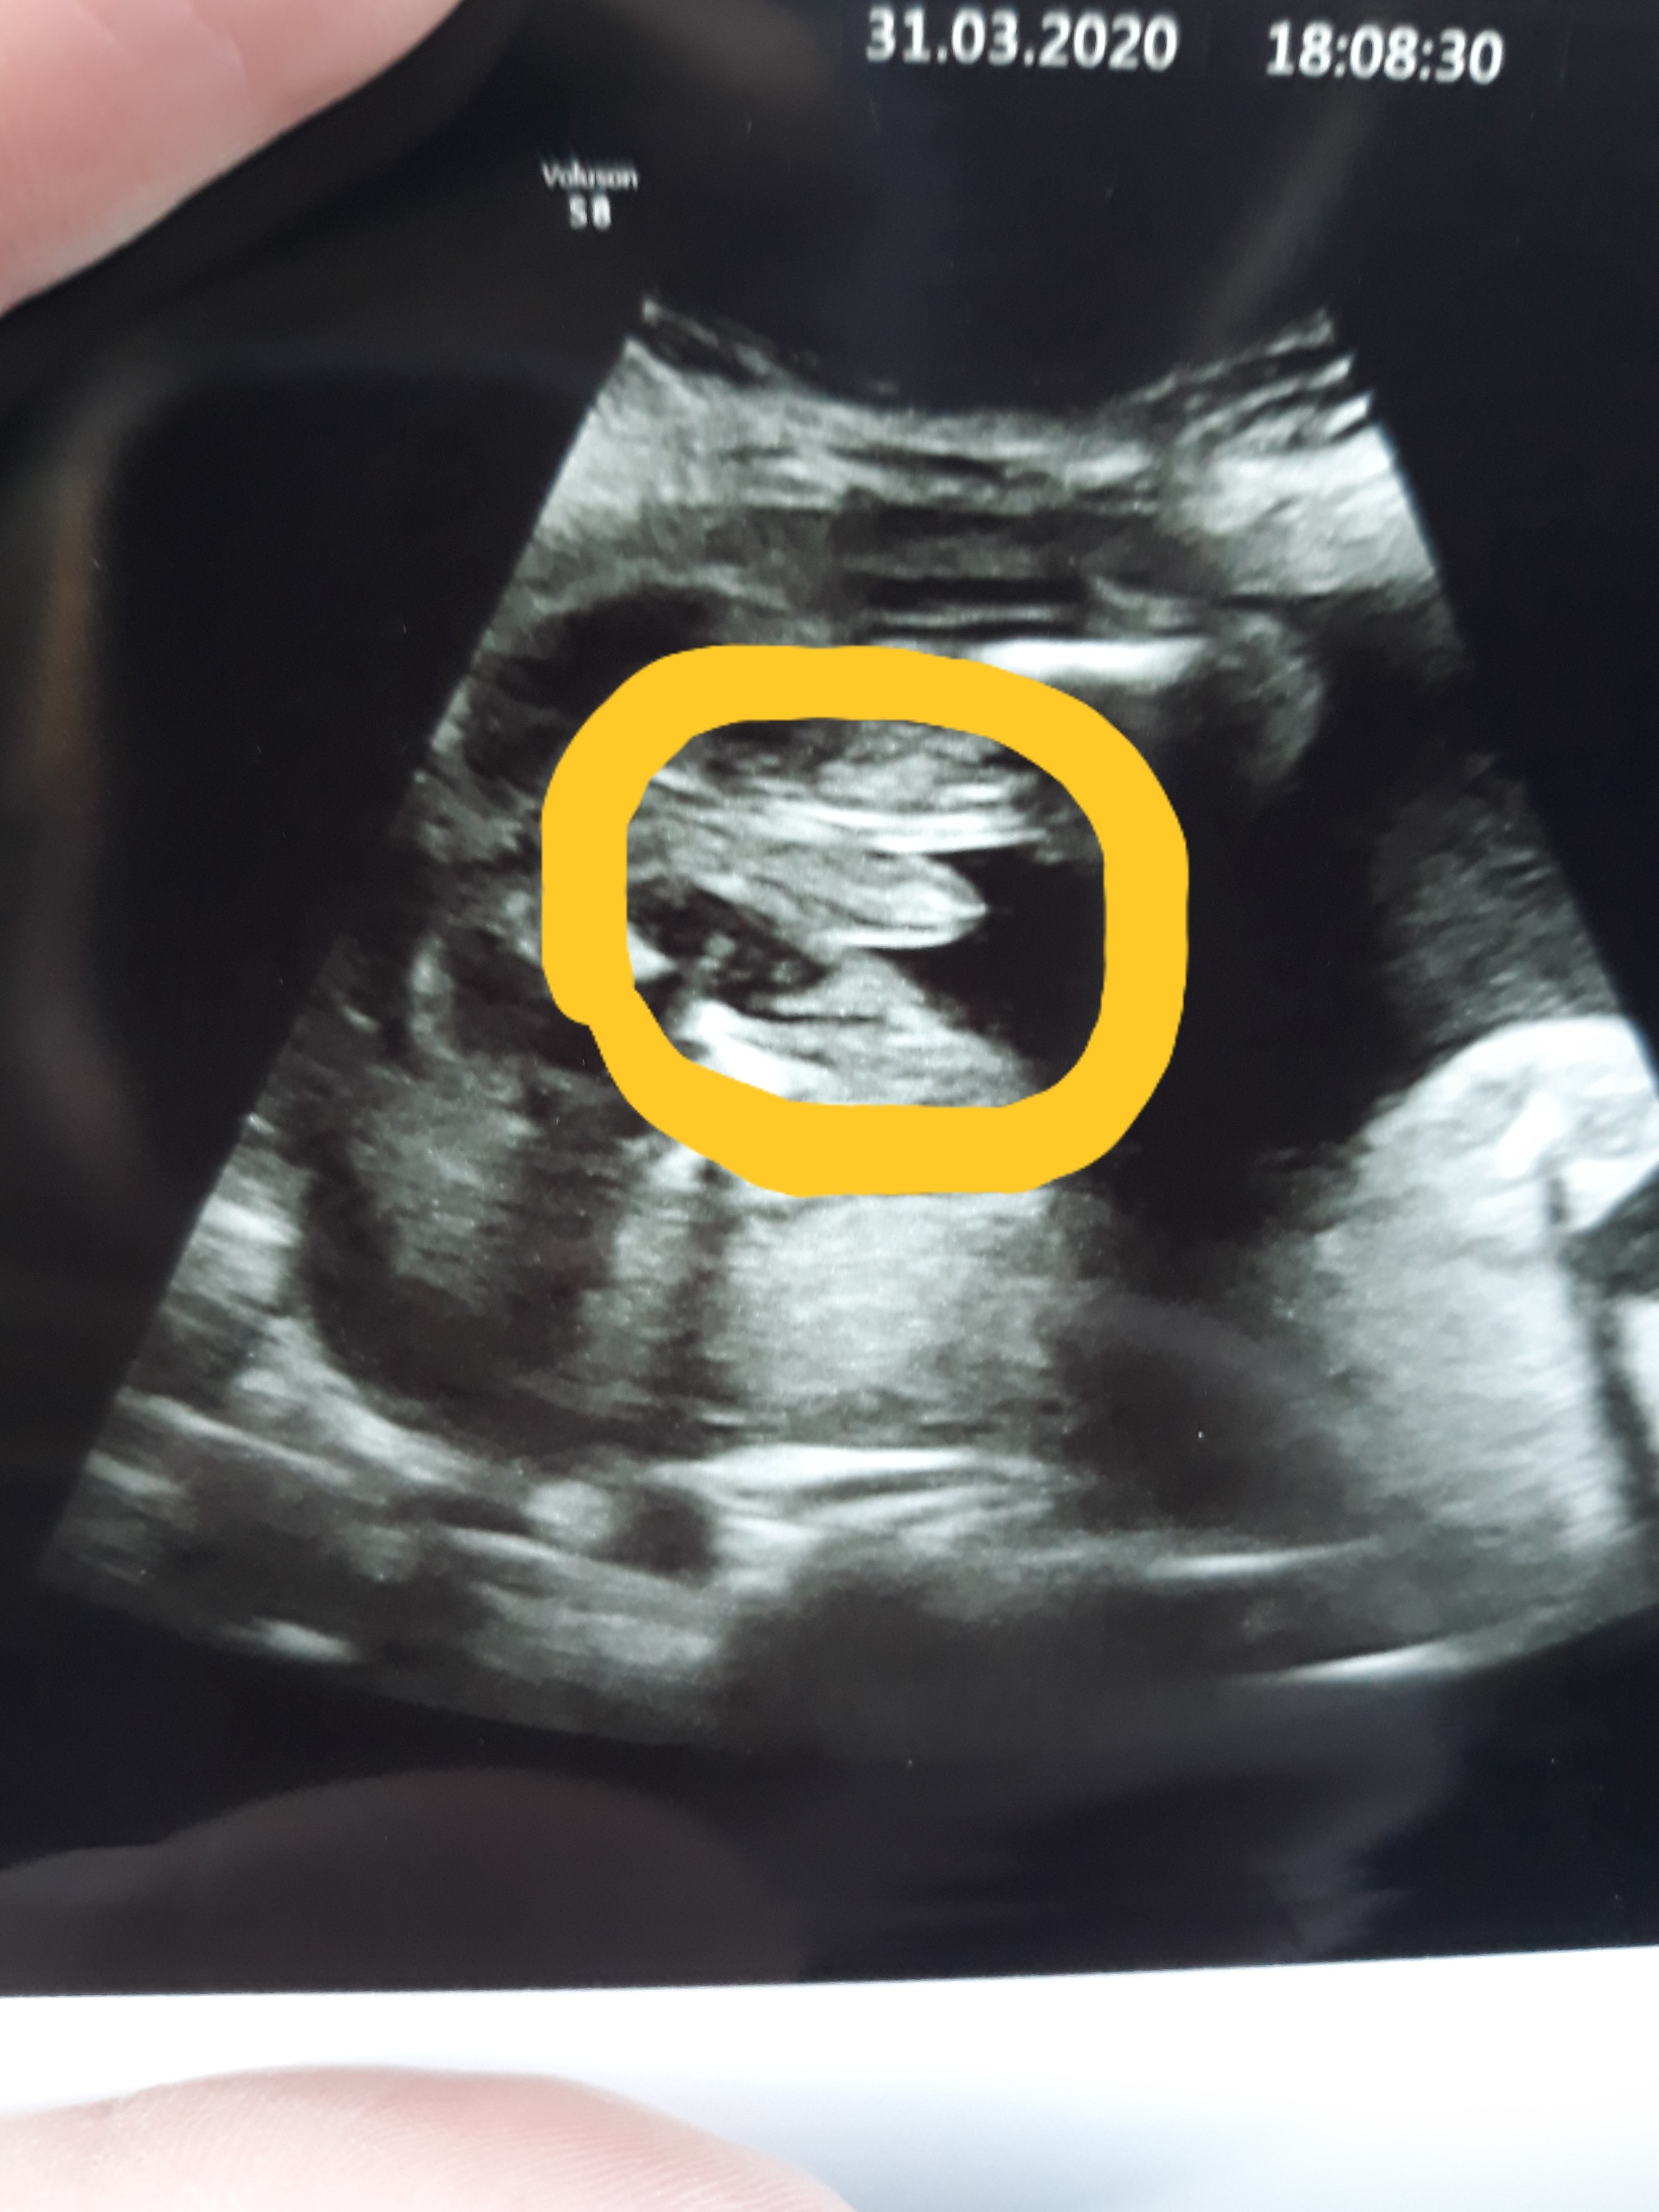

Usg chłopiec czy dziewczynka?

• 20200331_182849.jpg

20200331_182849.jpg

1,1 MB · Wyświetleń: 406